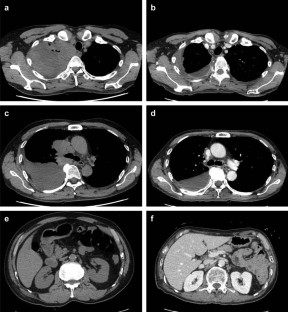

Fig. 1